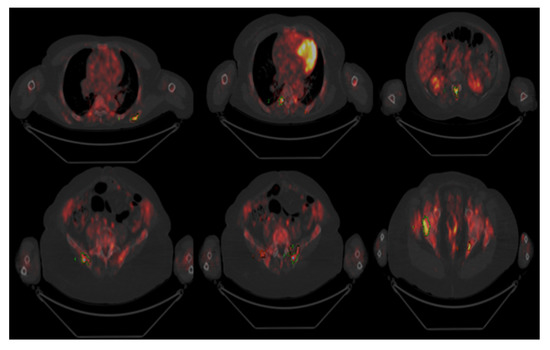

:1. Introduction